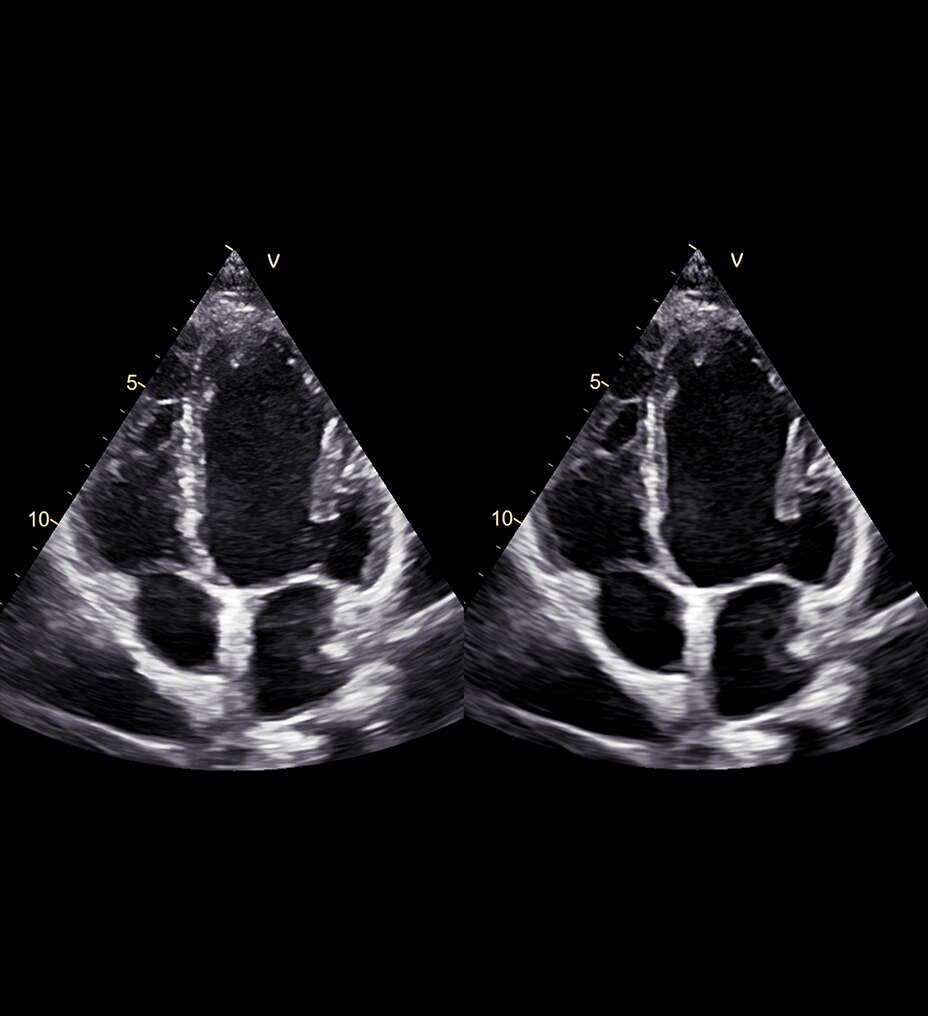

SIGNA™ Champion offre un design modulare con opzioni software e hardware pronte per soddisfare le priorità cliniche. Include strumenti di base e avanzati e soluzioni per la qualità delle immagini come AIR™ Recon DL e Sonic DL™. Queste applicazioni consentono non solo di ottimizzare i casi di routine, ma anche di operare in altri campi specifici come neurologia, apparato muscolo-scheletrico, cardiologia e oncologia. E non è tutto. SIGNA™ Champion è in grado di offrire configurazioni a 32, 48 e 64 canali per garantire la massima flessibilità e semplificare la configurazione delle bobine sulla base delle diverse anatomie.

AIR™ Recon DL potenzia le funzionalità della tua RM offrendo una qualità dell'immagine superiore con tempi di scansione ridotti.